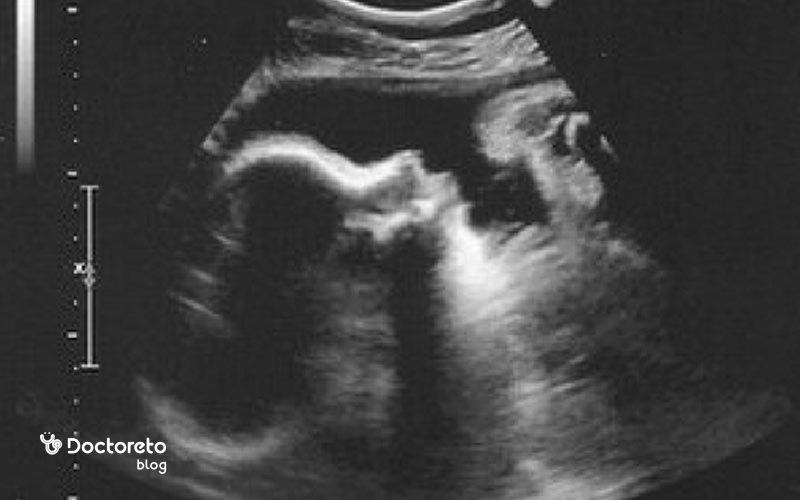

اندازه جنین 40 هفته به ۳۶ سانتیمتر میرسد. قد جنین از سر تا پا در حالت صاف ۵۱٫۵ سانتیمتر است. وزن جنین تقریبا نزدیک به ۳۶۰۰ گرم میشود. در این هفته جنین کاملا آمادگی زندگی خارج از رحم را دارد. اگر نوزاد در هفته ۴۰ بارداری به دنیا بیاید، میتواند تا فاصله حدود ۲٫۵ سانتیمتر را ببیند. به همین دلیل احتمالا صورت شما واضح دیده نمیشود.

اگر شما و همسرتان در اواخر بارداری با جنین صحبت کرده باشید، پس از تولد صدای شما را تشخیص میدهد. جالب است بدانید که تنها ۵٪ نوزادان در زمان تعیین شده به دنیا میآیند. وضعیت جنین در هفته ۴۰ بارداری معمولا سر به پایین است و سر در لگن درگیر است. صفحات جمجمه هنوز کمی انعطاف دارند تا عبور از کانال زایمان آسانتر شود. لایه ورنیکس کمتر از قبل است و ممکن است هنوز دیده شود.

با وجود کم شدن فضای رحم، جنین باید مثل الگوی همیشگی خودش حرکت کند. نوع حرکتها ممکن است بیشتر به صورت چرخش و جابهجایی حس شود تا ضربههای بزرگ، اما کاهش محسوس یا قطع حرکات علامت هشدار است. پس از تولد، رنگ پوست نوزاد در ساعات نخست میتواند متمایل به قرمز باشد و طی روزها و هفتههای بعد یکنواختتر میشود.